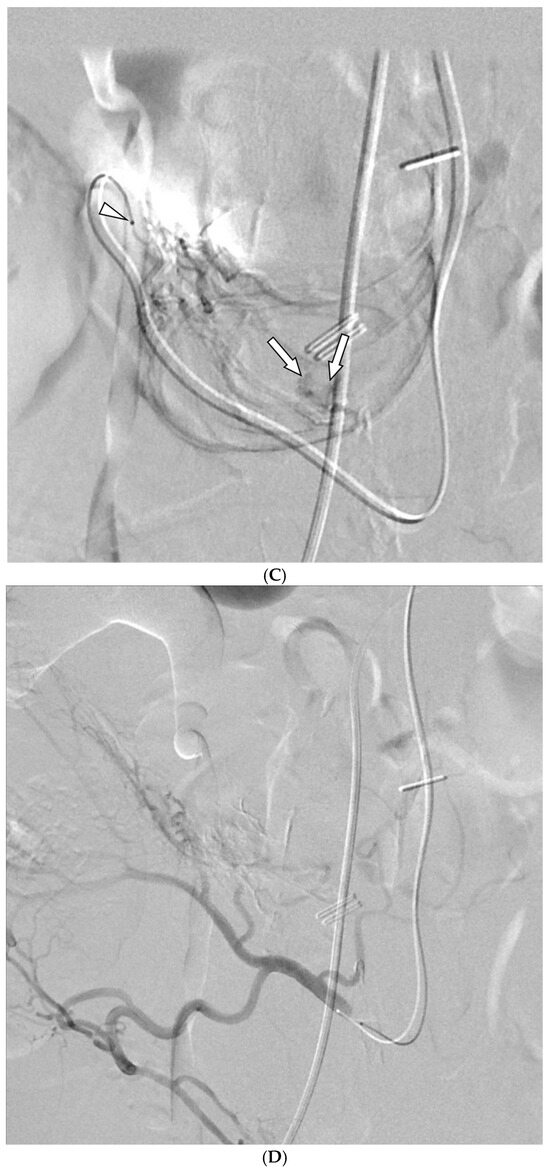

Embolization with Quick-Soluble Gelatin Sponge Particles for Lower Gastrointestinal Bleeding: A Multicenter Study

by Chang Ho Jeon, Seung Boo Yang, Woo Jin Yang, Ji Hoon Shin, Kyu-Pyo Kim, Jung-Hoon Park and Jin-Hyoung Kim

Medicina 2025, 61(11), 1964; https://doi.org/10.3390/medicina61111964 - 31 Oct 2025

Background and Objectives: Transarterial embolization (TAE) serves as a valuable alternative for gastrointestinal bleeding when endoscopy fails or is inaccessible. Quick-soluble gelatin sponge particles (QS-GSPs) dissolve rapidly and may reduce ischemic complications compared to permanent embolic agents. This study evaluated the safety and [...] Read more.

Background and Objectives: Transarterial embolization (TAE) serves as a valuable alternative for gastrointestinal bleeding when endoscopy fails or is inaccessible. Quick-soluble gelatin sponge particles (QS-GSPs) dissolve rapidly and may reduce ischemic complications compared to permanent embolic agents. This study evaluated the safety and effectiveness of TAE using QS-GSPs for acute lower gastrointestinal bleeding. Materials and Methods: This retrospective multicenter study analyzed patients who underwent TAE with QS-GSPs for acute nonvariceal lower GI bleeding between 2021 and 2024. Technical success (occlusion or stasis of blood flow in the target artery), clinical success (cessation of bleeding symptoms with hemodynamic stability during the week following TAE without major complications), and procedure-related complications were assessed. Results: A total of 29 patients (mean age 64.9 years) were included. Active bleeding was detected in 6 patients (20.7%) on angiography. Embolized arteries included jejunal (n = 7), ileal (n = 7), ileocolic anastomotic (n = 1), cecal (n = 2), colic (n = 7), and rectosigmoid (n = 5) arteries. QS-GSPs (150–350 μm (n = 10) or 350–560 μm (n = 19)), which dissolve completely within several hours, were used as the sole embolic agents. Technical and clinical success rates were 100% and 75.9% (22/29), respectively. Clinical failure occurred in seven patients (24.1%) due to persistent (n = 4) or recurrent (n = 3) bleeding within one week. Transient bowel ischemia occurred in two patients (6.9%) but resolved spontaneously. The clinical success rate did not differ significantly between patients with active bleeding (66.7%) versus those without (73.9%). Conclusions: TAE with QS-GSPs for acute lower GI bleeding demonstrated a favorable safety profile with clinical success exceeding 75%. Transient bowel ischemia occurred in 6.9% of patients with spontaneous resolution, and no bowel infarction was observed. Full article

Show Figures

Figure 1